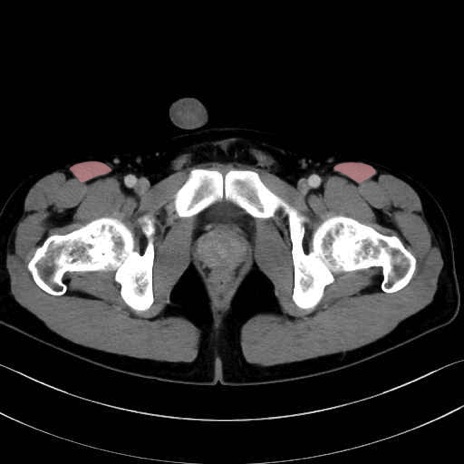

内閉鎖筋 (Obturator internus)

外閉鎖筋 (Obturator externus)

大腿方形筋 (Quadratus femoris)